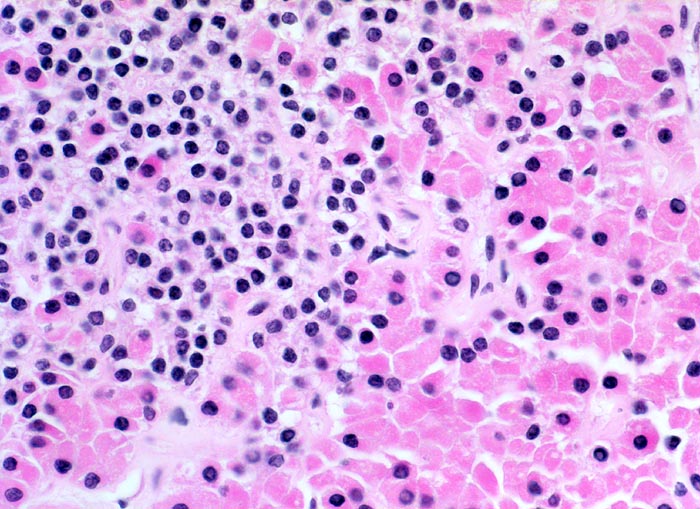

Morphologisch besteht bei sHPT eine Hauptzellhyperplasie. Makroskopisch findet sich eine meist ungleich ausgebildete Vergrösserung aller Nebenschilddrüsen. Die Grösse der Drüsen entspricht der Schwere und der Dauer des Stimulus. Die im früheren Stadium gefundene diffuse Hyperplasie mit Ersatz des Stromas und der Fettzellen durch chronisch stimulierte Hauptzellen (> 558) (> 559) geht im späteren Stadium in eine noduläre Hyperplasie („Pseudoadenome“) über (> 2358). Die regulierte Anpassung der Nebenschilddrüsen kann in eine Autonomie übergehen (tHPT) (> 3704). Morphologisch besteht in diesem Fall eine unregelmässige noduläre Hyperplasie. Gelegentlich entwickelt sich beim tHPT ein dominanter Knoten, der morphologisch nicht von einem Adenom bei pHPT unterscheidbar ist.

• Knotige vergrösserte Nebenschilddrüse. Abgrenzung der einzelnen Knoten durch breite Fibrosebänder.

• Hyperplasie lipidarmer Hauptzellen.

• Areale mit oxyphilen Zellen.

• Verminderter Fettgehalt (<<35%). Für normale Nebenschilddrüsen gilt: